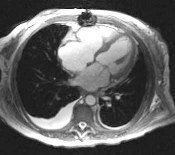

Aortna stenozaOsnovni hemodinamski poremecaj je opstrukcija isticanja krvi iz LK u aortu i gradijent pritiska u sistoli u nivou aortnog zalistka.Udarni volumen se dugo odrzava na normali u miru ali po ceni koncentricne hipertrofije miokarda LK. Pri naporu izostaje adekvatan porast udarnog volumena.U daljem toku i u miru UV pada i raste srednji pritisak u LP, PA, DK, a do znacajnog pogorsanja tegoba dovodi i nestanak efikasne atrijalne kontrakcije kod fibrilacija pretkomora ili AV disocijacije zbog toga jer je atrijalna kontrakcija u aortnoj stenozi znacajna za punjenje i efikasnu kontrakciju komora. Zbog hipertrofije miokarda , visokog sistolnog pritiska u LK i produzenog istiskivanja krvi iz nje, povecava se miokardna potrosnja kiseonika pa se i bez suzenja koronarnih arterija moze javiti miokardna ishemija. Dodatni doprinos tome imaju: pad UV i koronarnog protoka, kompresija hipertroficnog miokarda na koronarne arteraije spolja koji nadvlada perfuzioni pritisak u njima, kalcifikati na orificijumima koronarnih art. i udruzena ateroskleroza istih.